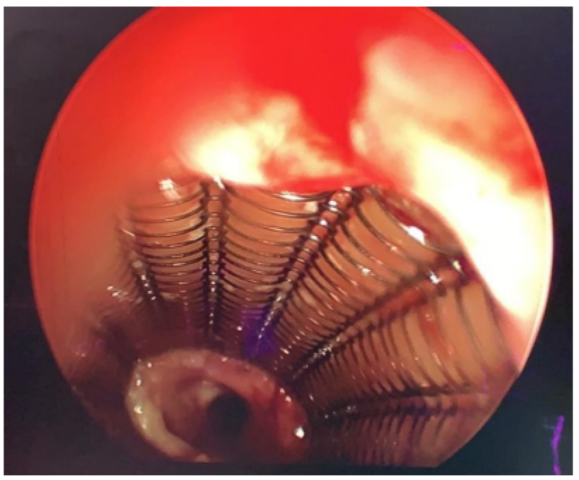

Image 3: Intra-operative image showing tracheal stent with granulation tissue at upper and lower end

The most common complication of stenting is formation of granulation tissue which is more often seen when upper edge of stent is located at or below the vocal folds as was seen in this case [2]. Metallic stents as in this case, are more prone to develop granulations especially at the proximal segment, as they are more rigid with multiple edges and produce circumferential pressure on tissues, leading to airway irritation [3].

Another complication is stent-associated respiratory tract infection (SARTI) which probably involves 1 in 5 patients with airway stent [4]. Stent migrations, stent fractures, sputum retention, halitosis may also occur [5,6].